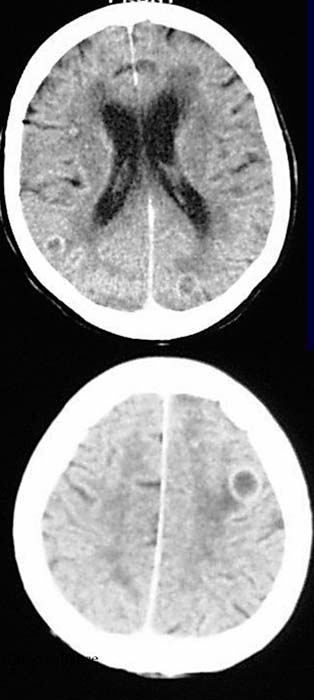

ANAMNESE / KLINIK:

Patient, 28 Jahre alt, HIV-positiv. Der Patient hat eine Katze zuhause

CCT mit Kontrastmittel.

Multiple beidseitige rundliche hypodense Areale. Ringförmiges Kontrastmittelenhancement.

DIAGNOSE:

Toxoplasmose

DIFFERENTIALDIAGNOSE:

Andere Abszesse, Metastasen, Glioblastom